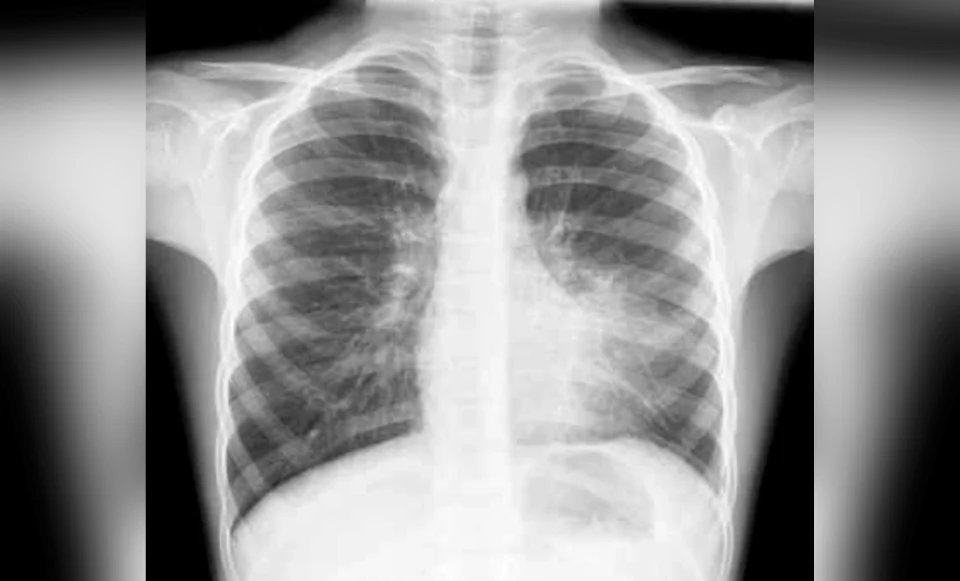

Paru-paru adalah organ yang luar biasa kompleks. Setiap kali anda menarik nafas, udara bergerak melalui trachea, masuk ke bronkus utama, bercabang kepada bronkus yang lebih kecil, kemudian bronkiol, dan akhirnya sampai ke alveolus — jutaan kantung udara kecil di mana pertukaran oksigen dan karbon dioksida berlaku.

Apabila jangkitan berlaku, ia boleh menyerang mana-mana bahagian dalam laluan panjang ini. Dan lokasi jangkitan menentukan betapa seriusnya keadaan.

Bronchopneumonia — jangkitan yang berkumpul di sekeliling saluran pernafasan besar (bronkus) — adalah jenis paling biasa. Ia selalunya disebabkan oleh bakteria atau virus biasa dan boleh dirawat dengan antibiotik jika dikesan awal.

Lobar pneumonia — jangkitan bakteria yang lebih agresif, membabitkan keseluruhan satu lobus paru-paru. Ini lebih serius, memerlukan rawatan lebih intensif dan tempoh pemulihan lebih lama.

Jangkitan coronavirus (COVID-19) — inilah yang membezakan dirinya dari semua jenis jangkitan paru-paru yang lain. Virus ini tidak berhenti di bronkus. Ia masuk sedalam-dalamnya — melalui trachea, bronkus utama, bronkus, bronkiol, sehinggalah ke alveolus di bahagian paling belakang paru-paru.

Hasilnya? Paru-paru bengkak. Cecair memenuhi saluran pernafasan dan alveolus. Fungsi pertukaran gas terjejas teruk. Dan yang paling mengejutkan — sistem imuniti tubuh sendiri boleh menjadi musuh. Bagi sesetengah pesakit, respons imun yang terlalu agresif menyebabkan sel-sel sihat turut diserang. Pesakit tidak sahaja batuk kahak, malah batuk tisu paru-paru yang telah reput (necrotic tissue). Ramai pesakit COVID-19 bukan mati kerana virus, tetapi kerana respons imuniti tubuh mereka sendiri.